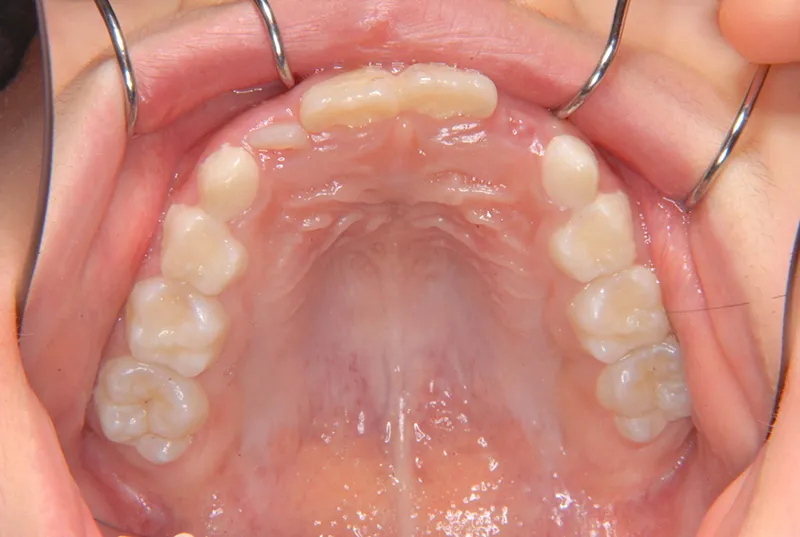

| 初診時年齢 | 小学校1年生(女性) | 主訴 | 受け口 | ||

| 診断名 | 叢生・反対咬合 | 装置名 | 拡大床 | ||

| 抜歯の有無 | 非抜歯 | 治療期間・通院回数 | 2年7ヶ月・21回 | ||

| 費用 | 481,890円(税込) | 費用内訳 | 相談料:1,050円 検査料:46,200円 施術料:210, 000円 装置料:105,000円 保定装置料:52,500円 調整料:3,150円×10回=31,500円 以上 消費税率5% / 調整料:3,240円×11回=35,640円 以上 消費税率8% | ブラケット・ ワイヤー |

付けずに治した |

| 特徴 |

固い食べ物が嫌い 乳歯列が綺麗に並んでいる ゆがんで生えている よく噛まないで飲み込む |

| 状態 |

永久歯が生える隙間がない(叢生) 受け口(口元が出ている/下顎前突/反対咬合) |

| リスク・副作用 |

矯正歯科治療に伴う一般的なリスク・副作用

|